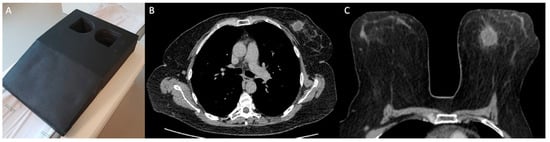

MDCT was performed with a specific protocol dedicated to breast evaluation, in prone position, using a specially made device (Figure 1), which reproduces the breast MRI coil. Exams were performed on a 160-slice MDCT scanner (Canon Aquilion Prime 160; Canon Medical Systems, Otawara, Japan), with a 0.5 mm slice thickness, before and after administration of 1–2 mL of the nonionic contrast material ioversol (Optiray 320; Mallinckrodt Medical Inc., St. Louis, MI, USA) per kilogram of body weight intravenously with a semiautomated power injector at a rate of 4 mL/s. The acquisition of chest images was performed 80–90 s after the contrast administration, which was previously reported as the optimal delay time to depict breast cancer [21]. Pre-contrast images were digitally subtracted from post-contrast images using a motion correction software (Sure Subtraction; Canon Medical Systems, Otawara, Japan) to improve the evaluation of enhancing lesions in the breast parenchyma and color-coded iodine maps were performed (Figure 2).

Figure 2. Example of chest MDCT with dedicated breast protocol. (A) Post-contrast axial image of chest MDCT in prone position showing a tumor in the right breast (arrow). (B) Subtracted imaging with color-coded iodine map showing the same tumor (arrow).